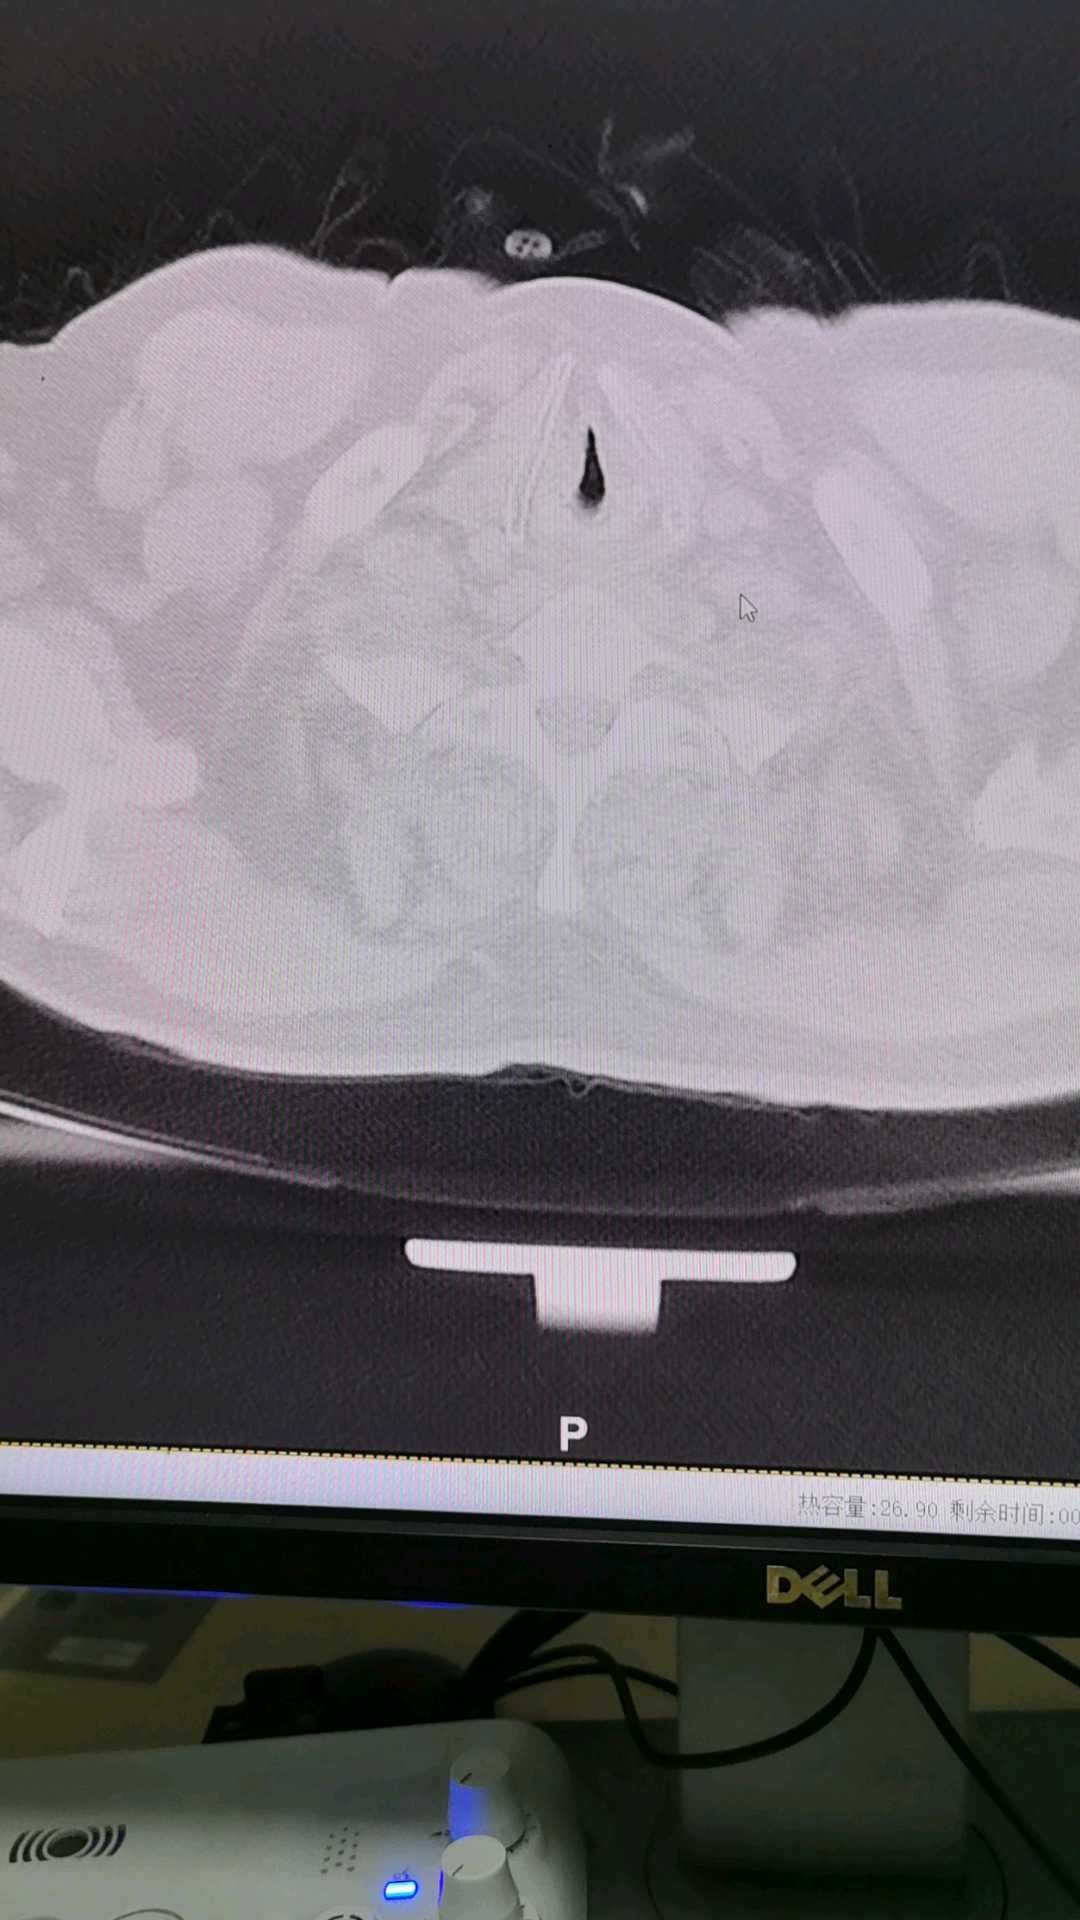

病例患者男 73岁,胸闷,胸痛许久,抗炎治疗一周后复查,来科室做的胸部CT。

患者男 73岁,胸闷,胸痛许久,抗炎治疗一周后复查,来科室做的胸部CT。

想请问老师,这是肺气肿啊!还是肺大泡